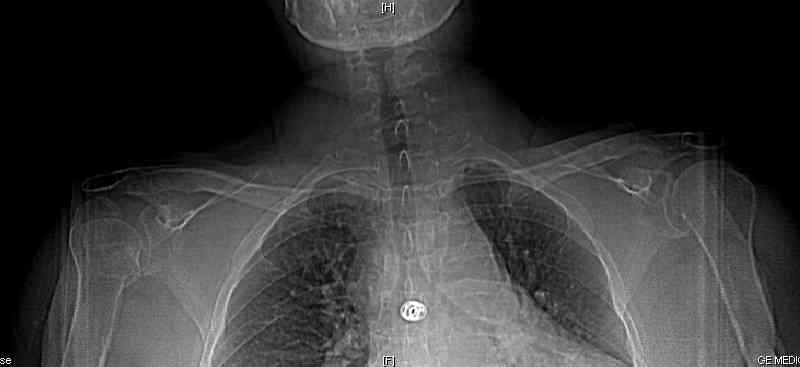

Уважаемые коллеги! Больная Н, 61 год, получила травму год назад. Закрытый оскольчатый перелом головки правого плеча, со смещением отломков.

Проведено консервативное лечение. Результаты представлены.

На Вашем снимке я вижу только перелом большого бугорка (сразу двух его фасеток) плечевой кости со смещением. Если это так. то смысла в эндопротезировании нет. Необходима о/репозиция, остеосинтез. Подобный опыт у меня был. Результаты - отличные. Но окончательное решение - только после R-графии плечевого сустава в косой проекции (30 градусов здоровым плечом вперед, 5-10 градусов сверху вниз), аксиальной проекции, или КТ.

Дополнение. Не смотрите на деформацию головки, там, конечно, был оскольчатый перелом. Но проблема не в этом. Необходимо восстановить "ключ" плечевого сустава - положение бугорка и анатомичную целостность комплекса вращающей манжеты.